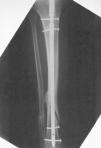

El tiempo medio operatorio fue de 63 minutos (mínimo: 45 y máximo: 90 minutos). Se utilizó un clavo de 8 mm en 29 casos y de 9 mm en 32; se produjo una fractura intraoperatoria de la cortical posterior (Fig. 1). La dinamización se llevó a cabo en una media de 9 semanas (mínimo: 5 y máximo: 20 semanas). La carga completa postoperatoria se inició a una media de 8 semanas (mínimo: 1 y máximo: 19 semanas) tras la intervención. Catorce (6,2%) de los 226 tornillos empleados se doblaron o rompieron (tres tornillos estáticos proximales, uno dinámico proximal y 10 tornillos distales). En tres pacientes el clavo no fue dinamizado antes de cargar peso. En uno de ellos se rompieron todos los tornillos y en dos se rompió el estático proximal y los dos distales (Fig. 2). En tres pacientes se rompieron los tornillos distales a pesar de que el clavo había sido dinamizado.

Figura 1. Rotura intraoperatoria de la cortical posterior de la tibia.Postoperatoriamente no hubo ningún síndrome compartimental, infección, embolia grasa o complicación neurológica. Dos pacientes desarrollaron distrofia simpaticorrefleja, tres presentaron un acortamiento de 6-10 mm y 13 pacientes (21%) desarrollaron dolor femoropatelar que desapareció al retirar el clavo. Todos los pacientes presentaron una movilidad completa de la rodilla. Hubo cuatro casos de rigidez del tobillo con falta del 20% de extensión. Sesenta pacientes (98%) volvieron a caminar sin claudicación y sin bastones y a subir escaleras normalmente. Todos ellos recuperaron su nivel de actividad previa a la fractura.